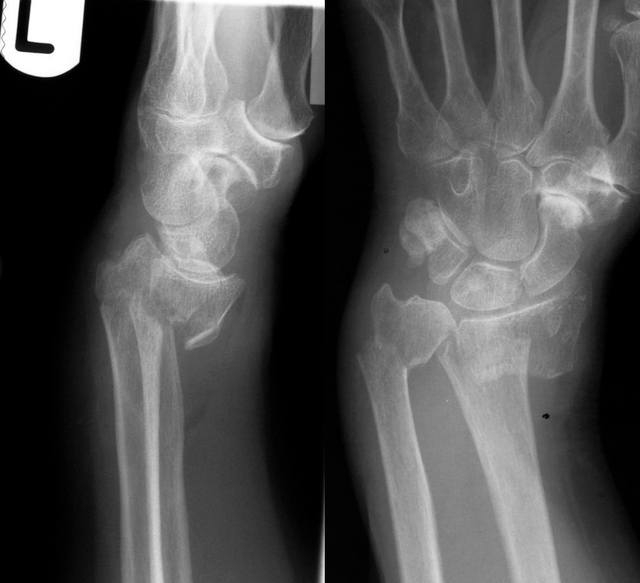

<br /><br />2) Goyrand - Smith: сгибательный перелом, смещения отломков и механизм травмы обратны описанному ранее<br /><br />

<br /><br />3) Barton: перелом описан в двух вариантах - волярном и дозальном и является частным случаем описанных выше переломов Смита либо Коллеса. Отличие - подвывих в лучезапястном суставе.<br /><br />Волярный Barton:<br /><br />